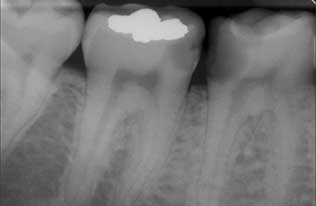

A cárie coronária é o tipo mais comum de cárie e aquela que ocorre na coroa do dente, quer seja nas superfícies oclusais (cárie oclusal), faces dos dentes ou entre os dentes.

Uma cárie pequena, mais especificamente incipiente ou no seu início, é ainda muito superficial, envolvendo apenas a superfície do esmalte (cárie de esmalte), e por vezes efetuam-se apenas procedimentos de remineralização, ficando a carie inativa. Numa cárie grande isso já não é possível, pois há já uma destruição em profundidade, envolvendo não só o esmalte como também a dentina e muitas vezes a polpa dentária.

A cárie aguda, geralmente afeta mais que um dente simultaneamente e normalmente apresenta uma cor clara. Tem tendência a progredir rapidamente, podendo em pouco tempo atingir a polpa e provocar dor aguda e forte. A cárie crónica, por sua vez, caracteriza-se por uma evolução lenta e intermitente, de cor mais escura e cavidades mais extensas, e com uma sintomatologia muito menos dolorosa.

A cárie recorrente, também chamada de cárie secundária, ocorre normalmente por acumulação de placa bacteriana em volta das restaurações, por falta de adaptação destas ou pela sua deterioração temporal, constituindo indicação para a substituição das mesmas.

O diagnóstico das cáries é efetuado pelo médico dentista através da observação direta complementada pela sondagem das superfícies dentárias, através de um “kitt” de exploração composto por sonda e espelho, e com iluminação própria.

Se notar alterações na cor dos dentes, como manchas brancas, amarelas, castanhas ou pretas, na parte lateral ou superior dos dentes (sulcos e fissuras), deverá consultar de imediato o seu médico dentista, pois pode estar perante uma carie ativa. A lesão de cárie entre os dentes pode também ser detetada ao passar o fio dentário, quando este rasga ou fica preso.